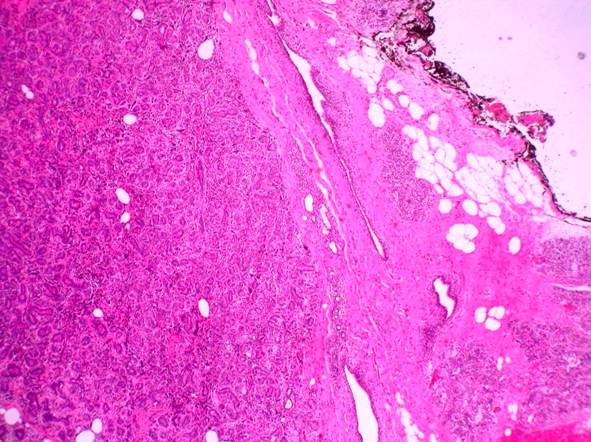

Microscopic examination of both specimens exhibited biphasic proliferation with pushing border, in which the stromal components displayed remarkable overgrowth (Fig.1). The stromal component was predominantly represented by adipose tissue with numerous hyperchromatic stromal cells and lipoblasts showing marked pleomorphism and atypia (Fig.2). Mitotic count in these areas was 2-3 per 10 high power fields. Highly atypical stromal cells were also intermingled with epithelial component. Only few foci with spindle cell stroma and leaf-like projections were seen (Fig.3). Malignant phyllodes tumor with heterologous liposarcomatous differentiation was diagnosed.

Fig 1

Panoramic view of the tumor showing tubular and malignant adipose components (H&E, x 40)